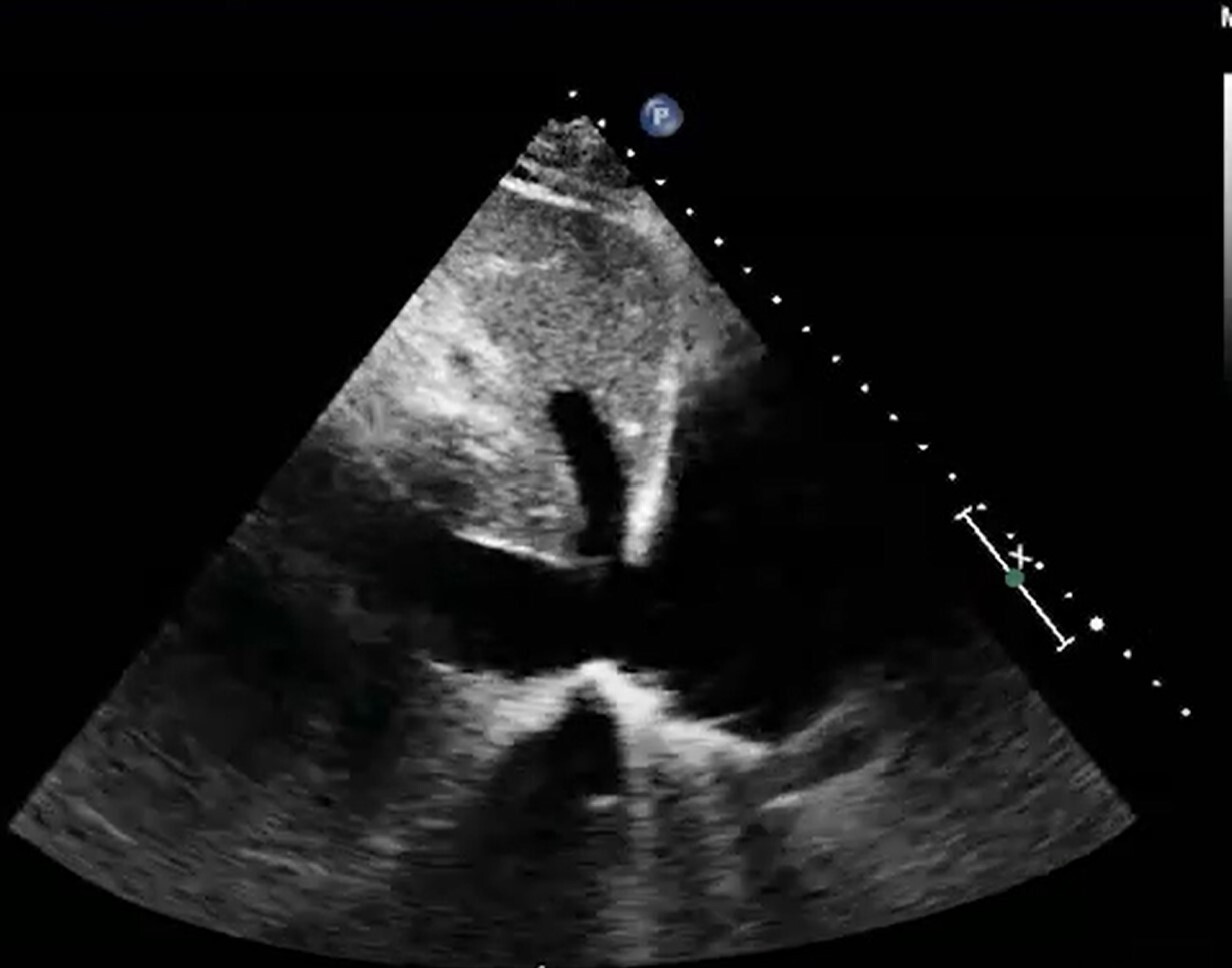

Parasternal long axis view - 3rd-5th interspace, just to the left of the sternum, probe indicator toward the right shoulder. RV, LV, LA, LVOT with aortic and mitral valves. Turn on doppler to evaluate for aortic regurgitation.